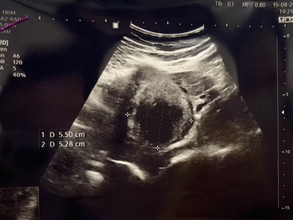

🤰🏻 มาค่ะ ยาวนิดนึงนะคะ เพื่อนๆ ถามกันมาเยอะ ขอเล่าตรงนี้เป็นประสบการณ์ชีวิตนะคะ 👶🏻 ก่อนอื่นต้องบอกก่อนว่าตอนนี้เราตั้งครรภ์ได้ 19 สัปดาห์แล้ว 🔸เริ่มมีอาการปวดท้อง ตั้งแต่คืนวันที่ 11 ส.ค. 66 และปวดมาก ถี่มากขึ้นช่วงบ่ายวันที่ 12 ส.ค. 66 บีบ-คลายเป็นระยะๆ ทุกๆ 3-5 นาที ครั้งนึงประมาณ 30 วิ เลยไปหาหมอที่ รพ.รัฐแห่งหนึ่งย่านศรีราชา เป็นหมอทั่วไป เพราะ รพ.ปิดวันแม่ หมอไม่ได้ส่งตัวให้หมอสูติฯ เอาฉี่ไปตรวจบอกว่า ติดเชื้อทางเดินปัสสาวะ ก็รับยาฆ่าเชื้อกลับบ้านอย่างเดียวไม่ได้ให้ยาแก้ปวด ทีนี้กลับมานอน คือปวดไม่ไหว ปวดแบบนอนไม่ได้เลยทั้งคืน เลยกังวลว่าจะเกี่ยวกับลูกไหม 🔹เช้าวันที่ 13 ส.ค. 66 เลยตัดสินใจไปรพ.เอกชนแห่งหนึ่งย่านศรีราชา เสียเงินตั้ง 3,500+ จะร้องไห้ สรุปคือ หมอบอกอาการปวดท้อง อาจจะแค่ปวดท้องเฉยๆ หรืออาจจะปวดจากสาเหตุติดเชื้อทางเดินปัสสาวะ ถ้าร้ายแรงคืออาการเริ่มต้นที่จะแท้ง อีแม่ใจหายวั๊บ! แต่ได้อัลตร้าซาวด์กับตรวจภายใน น้องยังปกติอยู่ หมอเองก็บอกไม่ได้ แต่ให้สังเกตอาการดู เลยขอพาราเค้ามากินด้วยเพราะปวดท้องมาก หลังจากหาหมอเสร็จก็คือกินยาแล้วยังปวดอยู่ ตื่นทุกชั่วโมง นอนไม่สบายตัว เวลาพลิกตัวหรือขยับตัวก็จะเจ็บท้อง 🔸วันที่ 15 ส.ค. 66 เริ่มกังวลว่ามันปวดนานเกินไปละ ไม่น่าใช่อาการปัสสาวะติดเชื้อละ เลยไปหาหมอ รพ.รัฐที่เดิมอีกครั้ง หมอบอกว่าดูจากผลฉี่รอบที่แล้วก็ไม่ได้ติดเชื้อทางเดินปัสสาวะนะ แต่เจอเม็ดเลือดแดงปนมา ถ้าติดเชื้อต้องเม็ดเลือดขาวมากกว่า เลยบอกว่าเม็ดเลือดแดงปนปัสสาวะเป็นมาตั้งแต่ก่อนจะท้องแล้ว คือตรวจเท่าไหร่ก็เจอ ก่อนท้องก็หาหมอนัดตรวจอยู่เรื่อยๆแต่หมอไม่ได้ทำการรักษาอะไรแค่นัดมาตรวจดูเป็นระยะๆ พอมีลูกก็เลยพักการรักษาไปก่อน เลยถามกลับไปว่าแล้วทำไมหมอคนก่อนถึงบอกว่าติดเชื้อทางเดินปัสสาวะ หมอไม่ตอบไร ให้ไปเปลี่ยนผ้าถุงมาอัลตร้าซาวด์ + ตรวจภายใน พบว่าลูกแข็งแรงดี น้ำหนักตามเกณฑ์ ปากมดลูกไม่ได้เปิด เลือดไม่ออก ไม่ได้เสี่ยงที่จะแท้ง แต่เจอเนื้องอกจากการอัลตร้าซาวด์เพราะหมอถามว่าปวดตรงไหนเลยชี้ หมอเค้าบอกว่า อาจจะเป็นเนื้องอกที่มีมาตั้งแต่ก่อนท้อง ตอนนี้ขนาดเกือบ 7 ซม. แล้วพอมีลูก เลือดมันไปเลี้ยงลูก เนื้องอกเลยขาดเลือด เลยทำให้ปวด แต่ไม่ใช่เนื้อร้าย ไม่ถึงกับเป็นมะเร็ง ยังไม่ต้องผ่าตัด แต่รอดูอาการติดตามผลช่วงหลังคลอด แล้วหมอก็จ่ายยาแก้ปวดชนิดแรงมาให้ I-Profen 400 เภสัชที่จ่ายยาก็ไม่อยากจ่ายให้เพราะมันแรง บอกให้นั่งรอ แล้วเค้าก็โทรหาหมออีกทีว่าจ่ายแน่ใช่ไหม หมอบอกจ่ายให้ และนัดสัปดาห์หน้า แต่ถ้ากินแล้วหายปวดก็ไม่ต้องมาหาหมอแล้ว ก็ให้หากับหมอที่ฝากครรภ์คลินิกประจำไป 🔹ด้วยความที่ยามันแรงและกังวลว่ากินได้จริงหรอ และอยากได้ความชัวร์อีก เลยไปหาหมอที่ฝากครรภ์ หมอที่ฝากครรภ์เขาซาวด์ดูเนื้องอกให้ใหม่ ขนาดจริงๆคือ 5.5x5.2 ซม. แล้วเค้าบอกว่า เคยเจอเคสที่ก้อนเนื้อใหญ่กว่านี้ เค้าก็มีลูกได้ปกติ ตอนนี้ทำไรไม่ได้ นอกจากประคับประคองการตั้งครรภ์ กินยาแก้ปวดเมื่อรู้สึกปวด หรือต้องไปฉีดยา เพราะถ้าเริ่มจะ 8เดือนหมอก็จะไม่ให้กินยาอันนี้แล้ว ต้องคลอดก่อน ถึงจะมาดูเรื่องเนื้องอกอีกที ไม่ได้ส่งผลอันตรายกับลูก แต่แม่จะปวดมาก เพราะว่าเลือดมาเลี้ยงที่ลูก ไม่ไปเลี้ยงที่เนื้องอก #เรามีเนื้องอกเป็นเพื่อนลูก